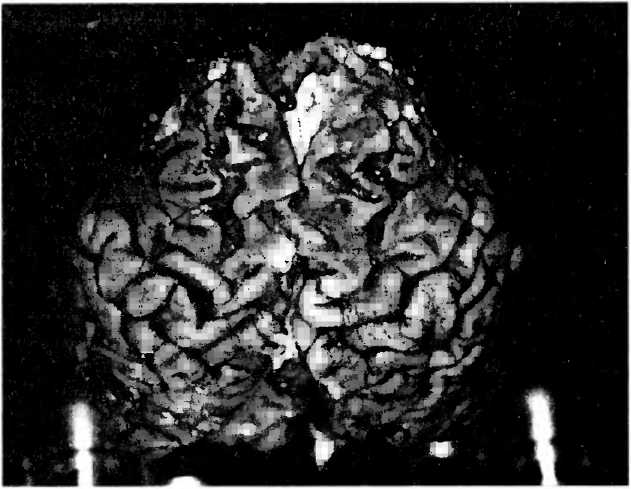

Болезнь Альцгеймера представляет собой наиболее часто встречающуюся форму деменции. Поскольку население в целом стареет, а возраст является важнейшим фактором риска для этой болезни, следует ожидать, что число жертв этой болезни в ближайшие 30 лет удвоится. Диагноз болезни Альцгеймера можно с уверенностью ставить в тех случаях, когда умерший пациент страдал деменцией и, кроме того, под микроскопом видны были характерные изменения мозга (рис. 28). Потому что существуют и другие формы деменции, которые только по виду мозговой ткани можно было бы с уверенностью отличить от болезни Альцгеймера.

Рис. 28. В серебряном окрашивании по методу Галльяса среза коры больших полушарий 85-летнего пациента с болезнью Альцгеймера под микроскопом видны два типичных поражения мозга: содержащие амилоид большие круглые бляшки между нервными клетками и клубки в нервных клетках, отмеченные черным.

Масштабная линия обозначает длину в 100 микрон.